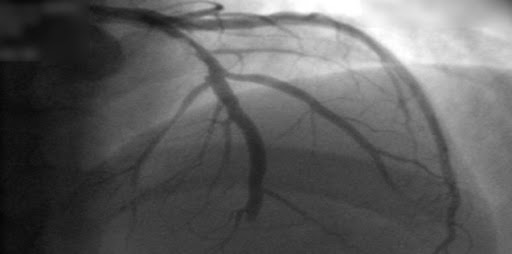

En el tratamiento de la hipertensión, hay evidencia de certeza moderada de que los diuréticos reducen los eventos cardiovasculares graves y la insuficiencia cardíaca congestiva más que los antagonistas del calcio. Existe evidencia de certeza baja a moderada de que los antagonistas del calcio probablemente reducen los eventos cardiovasculares graves más que los betabloqueantes. Existe evidencia de certeza moderada a baja de que los antagonistas del calcio redujeron el accidente cerebrovascular al compararlos con los inhibidores de la enzima convertidora de angiotensina (IECA) y redujeron el infarto de miocardio al compararlos con los antagonistas de los receptores de angiotensina (ARA), pero aumentaron la insuficiencia cardíaca congestiva en comparación con los IECA y los ARA.  Cochrane Database of Systematic Reviews, 17 de octubre de 2021